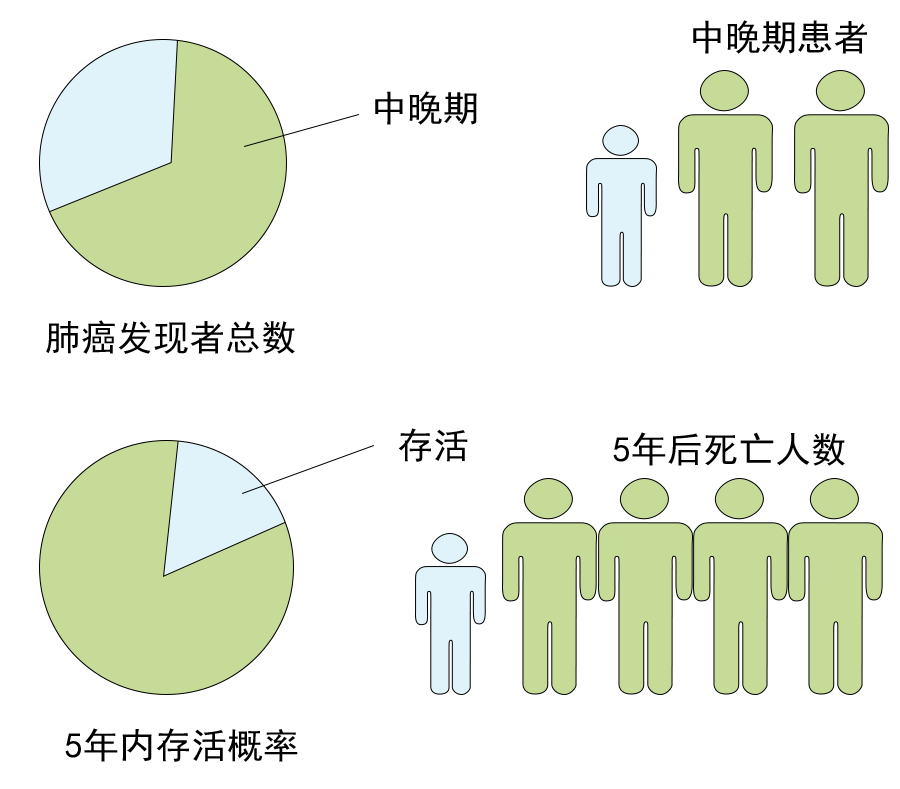

没想到我这么大岁数,切掉一个肺叶的十年后,再次做这么复杂的手术还这么顺利。 D大爷今年72岁,10年前曾行左肺上叶切除+淋巴结清扫术,手术标本病理为腺癌,术后给予了四次化疗。当时的胸部CT即可见右肺上叶小结节影,术后定期复查,病灶缓慢增大,一度略有缩小,此后再次逐渐增大。结合患者一直随访的影像学资料,杨如松院长考虑为右上肺新发恶性肿瘤。 2015年胸部CT 2020年胸部CT 虽然患者及其家属手术的意愿非常强烈,但此手术难度较高,原因在于: 1.患者年龄较高,手术风险大。 2.患者10 年前肺癌手术切除左边肺的一半,肺功能丧失较多。 3.病灶在右上肺的深部,切除有一定的难度。 为了保证患者术后的生活质量,我们不能够做肺的楔形切除这样的简单肺手术,而需要行肺段的切除。 EDDA重建提示病灶位置深 如果放在以前该患者就只能做做放化疗等保守治疗了。幸亏南京胸科医院目前引进了各种国内乃至国际上的先进技术。 如EDDA术前三D成像技术;只有单一3cm长切口的单孔胸腔镜技术;近红外荧光镜肺段、亚肺段精准定位技术等。 有了这些技术,杨如松院长心中有了底气。杨院长根据病人的情况设计手术方案,尽量减轻手术创伤,让接受第二次肺部复杂手术的高龄病人能够耐受,并且在术后能够顺利恢复。 根据术前EDDA三维重建,患者进行了单孔荧光胸腔镜S1a+2a切除术,术中先用ICG反染法确定段间面,再用膨胀萎陷法印证段间面,这保证了手术切除的精准性。 患者术中快速病理为贴壁型腺癌,这也印证了杨如松院长术前对患者肺结节良恶性的判断。 术后5天,D大爷非常顺利的出院了。出院前开心的窦大爷连声感谢杨如松院长:没想到我这么大岁数,切掉一个肺叶的十年后,再次做这么复杂的手术还这么顺利,谢谢、谢谢! 基本情况